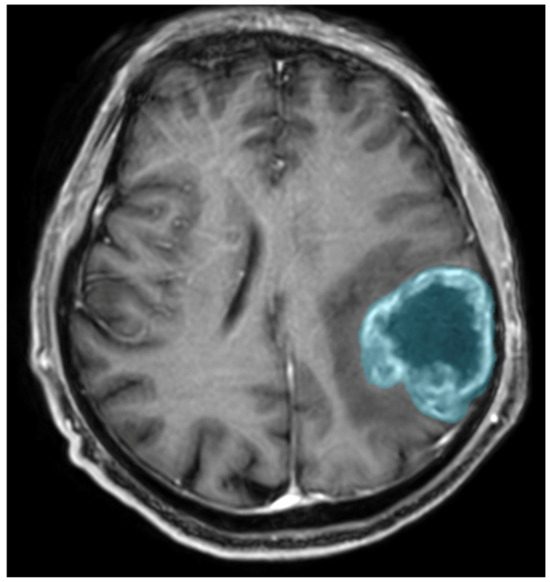

Preoperative MRIs were analyzed using Syngo.Via VB10, Research Frontier, Siemens Healthineers. Segmentation of the lesion was performed semi-automatically by a single reader (a fourth-year radiology resident). The 2D region of interest (ROI) was marked on the axial view of contrast-enhanced T1-weighted imaging (CE T1WI) on the cross-section in which the tumor had the largest area, and the zone of visible contrast enhancement was identified as the tumor boundary. An example of semi-automated tumor segmentation is shown in Figure 4.

Figure 4. Glioma CNS WHO 4 in the left parietal lobe. T1-weighted image after administration of contrast agent; the blue color was used to mark the tumor segmented by the semi-automated method.